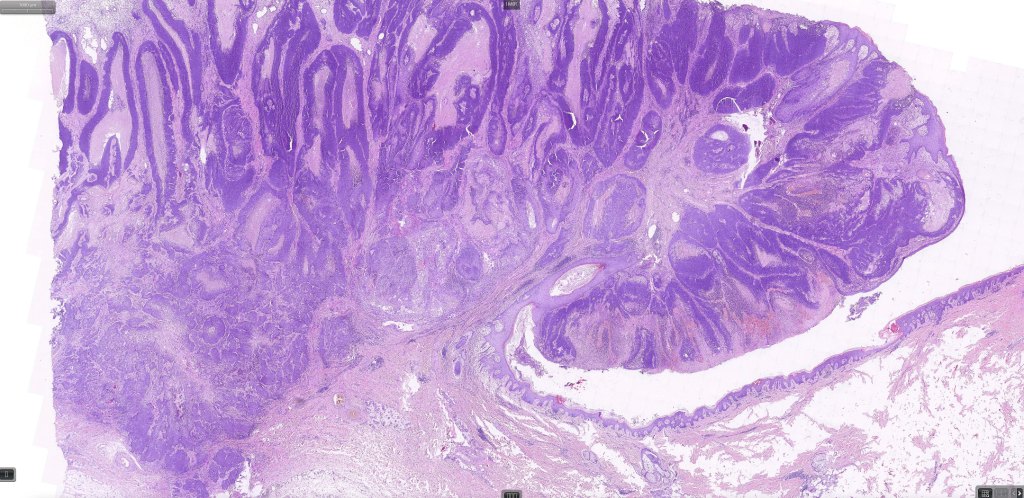

•Well differentiated lobular growth pattern though to a poorly differentiated tumor often showing a diffuse, infiltrating border which may extend into the subcutaneous fat

•May be associated with Pagetoid spread

•Well differentiated examples can be deceptive unless one looks carefully for pleomorphism, necrosis, excessive mitotic activity and abnormal mitoses. Be careful diagnosing sebaceous adenoma, particularly large examples arising in the elderly

•Periocular shave biopsies can be misleading and easily mistaken for Bowen’s disease

Sebaceous carcinoma from a patient with Muir-Torre syndrome kindly shared by Dr. Antonina Kalmykova.